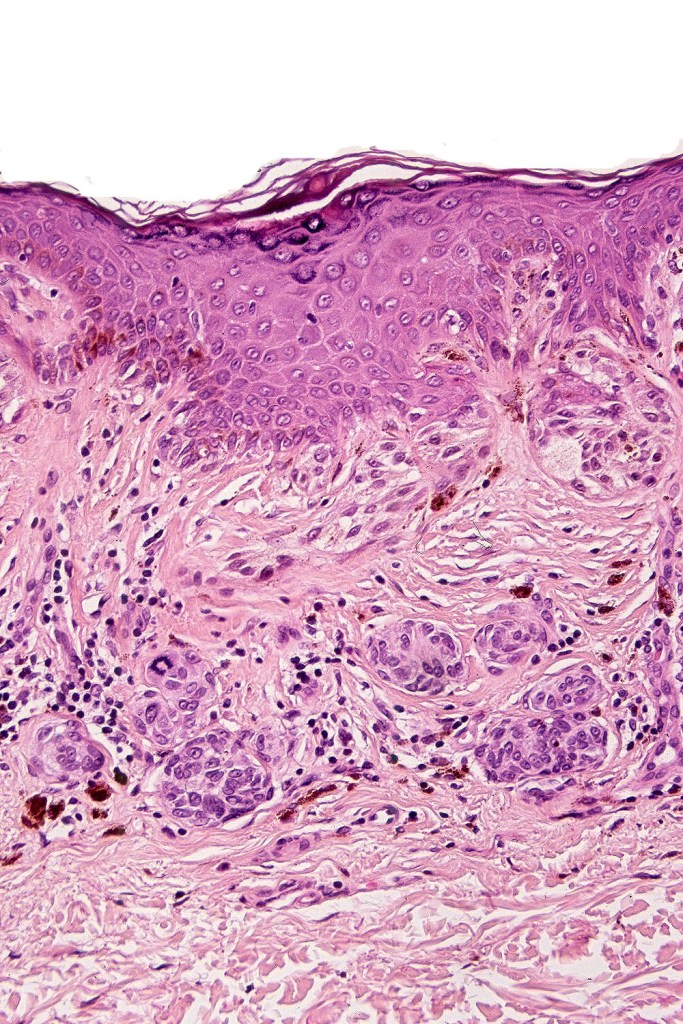

Histological features

•Architectural disorder- lentiginous and nested, nests abnormally located (at the sides of the rete ridges & overlying the dermal papillae in addition to the tips of the rete ridges rather than solely occupying the tips of the rete ridges as is seen in banal nevi), horizontal orientation & bridging between junctional nests (this should not be confused with bridging between adjacent rete ridge squamous epithelium)

•Abnormal fine pigmentation (dusty)

•Cytological atypia- mild, moderate & severe (or more recently, low & high grade (WHO). The problem with the new WHO classification is that mildly dysplastic nevi are now included with the banal nevus category and moderate is low grade and severe is high grade. In all likelyhood, most pathologists will include mild & moderate atypia in the low grade category.

•Variation in the degree of atypia within any one lesion is commonly present

•Rare mitoses

•Pagetoid spread absent

•Host response- eosinophilic & lamellar fibroplasia, increased vascularity, lymphocytic infiltration & pigment incontinence

•In compound lesions, the nest size should be smaller than the junctional ones and the degree of atypia the same or less

•No dermal mitoses